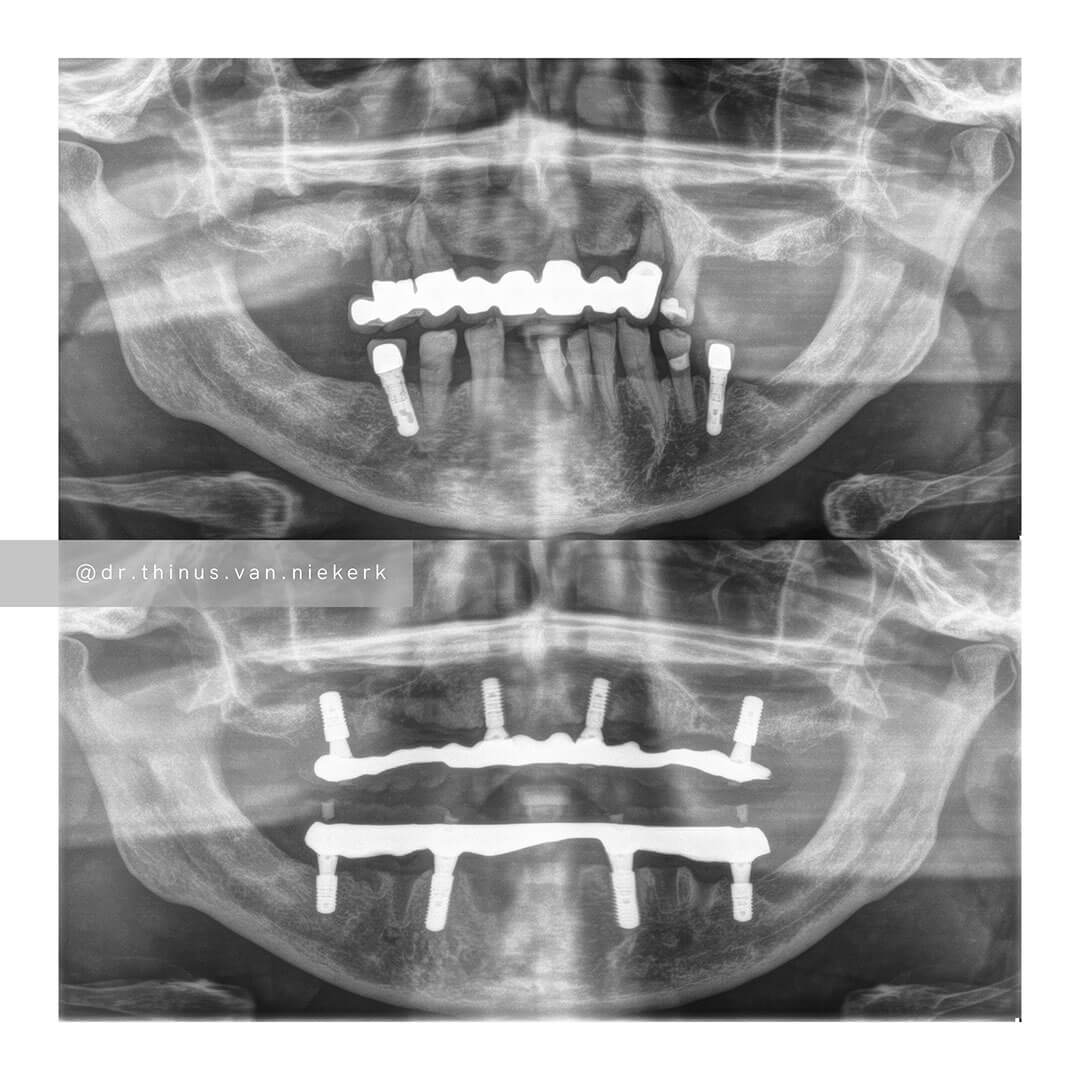

The pictures below are before and after images from a typical All-on-Four Rehabilitation.

Besides the glaring obvious improvement of the smile and teeth, you may also notice a

huge change in the upright (vertical) dimension of the patient’s face. This restoration of

vertical height is a big deal in any restorative case as it puts the joints and muscles in

better relation. This alone resolves many of the commonly associated symptoms such

as headaches, earaches and muscle spasms. These symptoms may range from a

mild intensity to complete debilitation.

COMMENTS

This was a landmark case for our clinic – being the first fully digitally-planned upper and lower rehabilitation. This case demonstrated the power and effectiveness of digital implant-surgery planning and CAD design software. No adjustments were needed at the placement of the final lower prosthesis.